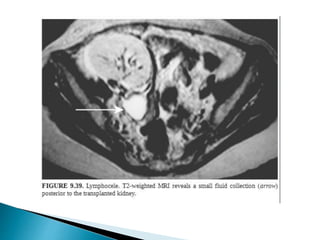

2. Urinomas

3. Lymphocele

4. Abscess